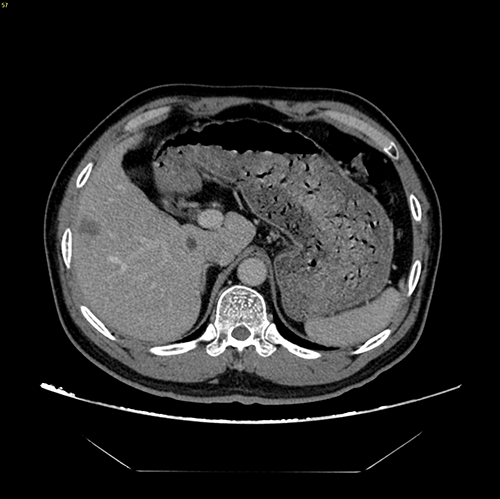

S56 肝癌--腹腔镜S56部分切除